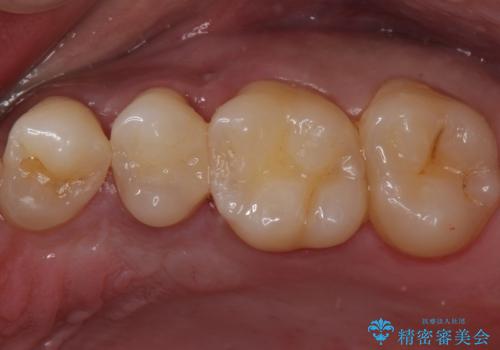

歯と歯の間の虫歯 セラミックインレーでの治療

- 検査の結果虫歯が見つかった患者様です。

レントゲン画像と視診から詰め物で対応可能と判断したためインレーでの修復をしていきます。

- 左上5 セラミックインレー/77,000円費用は治療当時の料金となります

適合の良いインレーは段差がない上にセラミックは汚れがつきにくい材料であるため今後の虫歯発生リスクを抑えることに繋がります。